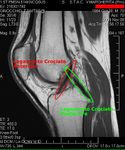

وتتصل عظمة الفخذ والظنبوب (عظمة الساق السفلى الكبيرة) بثلاث طرق هي : 1 – بالأربطة (أنسجة قوية شبيهة بالوتر)، 2 – بالعضلات، 3 - بمحفظة زليلية. وتحيط المحفظة الزليلية بالمفصل. وأربطة الركبة هي الموصلات الأقوى بين عظمة الفخذ والظنبوب. وهذه الأربطة تمنع العظمات من التزحزح عن مكانها.